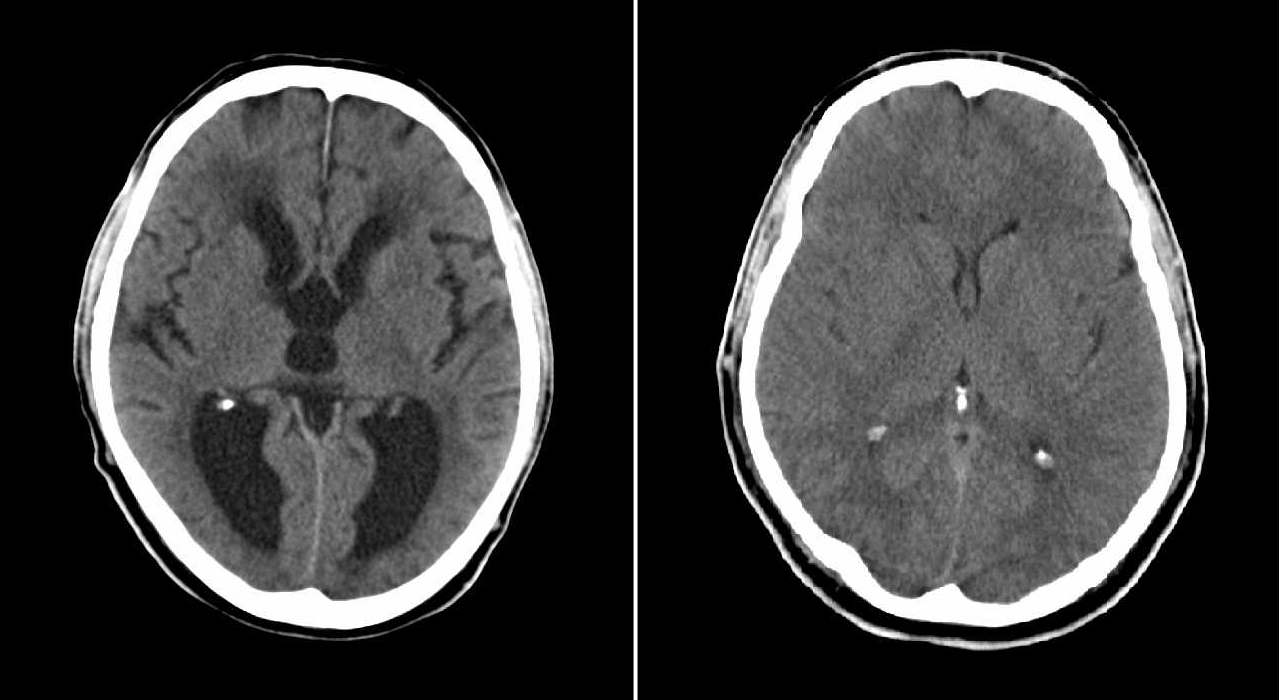

A side-by-side comparison of a brain with hydrocephalus (left) and a brain without hydrocephalus (right) as documented through computed tomography scans. Image credit: MBq via Wikimedia Commons (public domain), edits by Rachel Lense for The Science Writer

Lily has hydrocephalus, a condition caused by an excess of cerebrospinal fluid (CSF) — a clear, champagne-colored liquid that surrounds our brains and spinal cords. When she was a baby, a brain tumor blocked the natural flow of CSF, flooding her brain and filling the already crammed quarters of her cranium, raising the pressure to unmanageable levels. Surgery and radiation removed the tumor, but the hydrocephalus remained. The solution: a ventriculoperitoneal shunt placed in her head to drain the excess CSF that her brain cannot absorb into her abdomen.

As a baby, a tumor invaded Lily’s brain and grew aggressively, staking its claim in an already crowded environment. The tumor blocked the flow of CSF, and her ventricles could not keep up with the non-stop production. When we looked at her CT scans, doctors would point out her swollen ventricles, which looked like lakes of dark water. It reminded me of an aerial view of hurricane-flooded landscapes, structures unrecognizable underneath the flood.